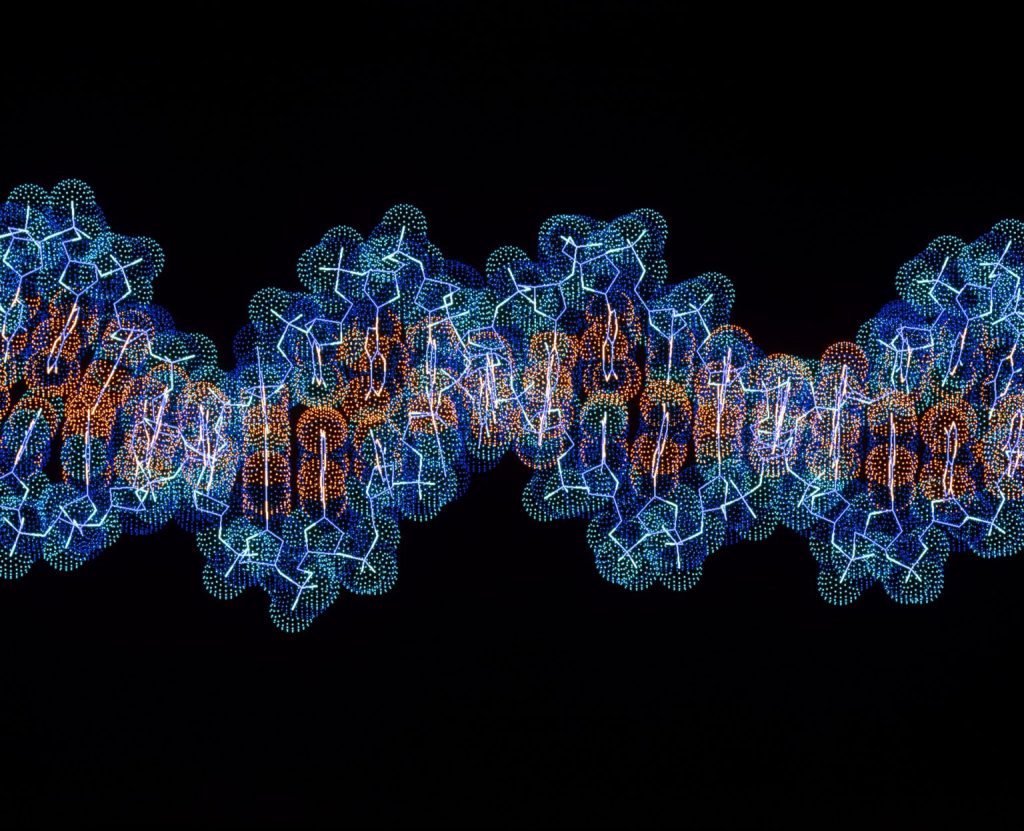

A través de la diversidad genética, se espera mejorar la atención médica de grupos minoritarios.

El programa All of Us, ha generado resultados prometedores al centrarse en el análisis genético de grupos históricamente oprimidos. Hasta ahora, se han recopilado datos de 245 mil genomas, descubriendo más de 275 millones de marcadores genéticos nuevos.

Visibilización genética

La falta de diversidad genética ha sido una preocupación ya que 78% de los participantes en la mayoría de los estudios son de ascendencia europea. Esto se traduce en investigaciones basadas en datos no representativos de la población general, que podrían afectar en la preservación de la salud.

La información obtenida ha resultado valiosa, especialmente en genomas latino y afroamericanos, que han estado subrepresentados en otros biobancos genéticos. La base de datos incluye encuestas, antecedentes de salud y registros a través de dispositivos portátiles, convirtiéndose en uno de los recursos más poderosos en investigación genética.

Se ha demostrado su utilidad en estudios sobre la diabetes tipo 2 al identificarse 611 marcadores genéticos, de los cuales 145 eran desconocidos. Como resultado, este tipo de descubrimientos pueden informar el desarrollo de tratamientos personalizados y mejorar la atención médica.

La iniciativa también ha mejorado los modelos de puntajes de riesgo poligénico, que evalúan el riesgo de una persona a desarrollar una enfermedad basada en su genética. El objetivo es mejorar estos puntajes para 23 condiciones, priorizando padecimientos como la enfermedad coronaria y diabetes.